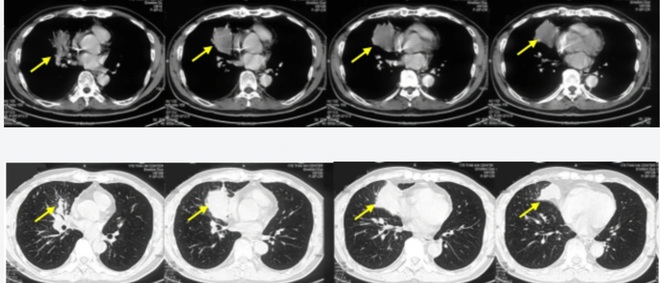

Hình ảnh chụp cắt lớp vi tính lồng ngực khối u thùy dưới phổi phải kích thước 6,1 x 4,8 cm (mũi tên).

Tại Bệnh viện Bạch Mai, bệnh nhân được chụp cắt lớp vi tính phát hiện khối u phổi phải, nhập viện điều trị. Trước đó, bệnh nhân có tiền sử hoàn toàn khỏe mạnh.

Kết quả chẩn đoán xác định bệnh nhân ung thư phổi phải di căn xương đa ổ giai đoạn 4, với kết quả mô bệnh học là ung thư biểu mô tuyến, PDL1 (+), đột biến E746_A750 trên exon 19.